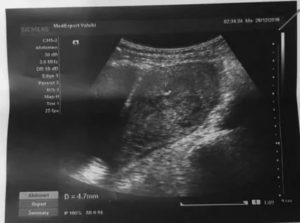

Какой срок позволяет увидеть плодное яйцо и определить его размеры? Увидеть эмбрион можно, когда плодное яйцо будет не менее 1 см. Если произошла задержка менструального кровотечения на неделю, к этому времени процесс гестации ориентировочно достиг 6 недель.

К этому периоду при диагностике высокоточным аппаратом плодное яйцо уже видно. Определить наличие сердцебиение эмбриона и рассмотреть его строение пока невозможно.

Внутренний диаметр плодного яйца в этом сроке составляет порядка 22 миллиметров. Начиная с 5 недель беременности его размер увеличивается на 1-2 мм.

Главным и пока единственным измеряемым размером плода является копчико-теменной размер. В 6 недель он составляет 6 миллиметров. КТР равен длине эмбриона от головки до копчика.